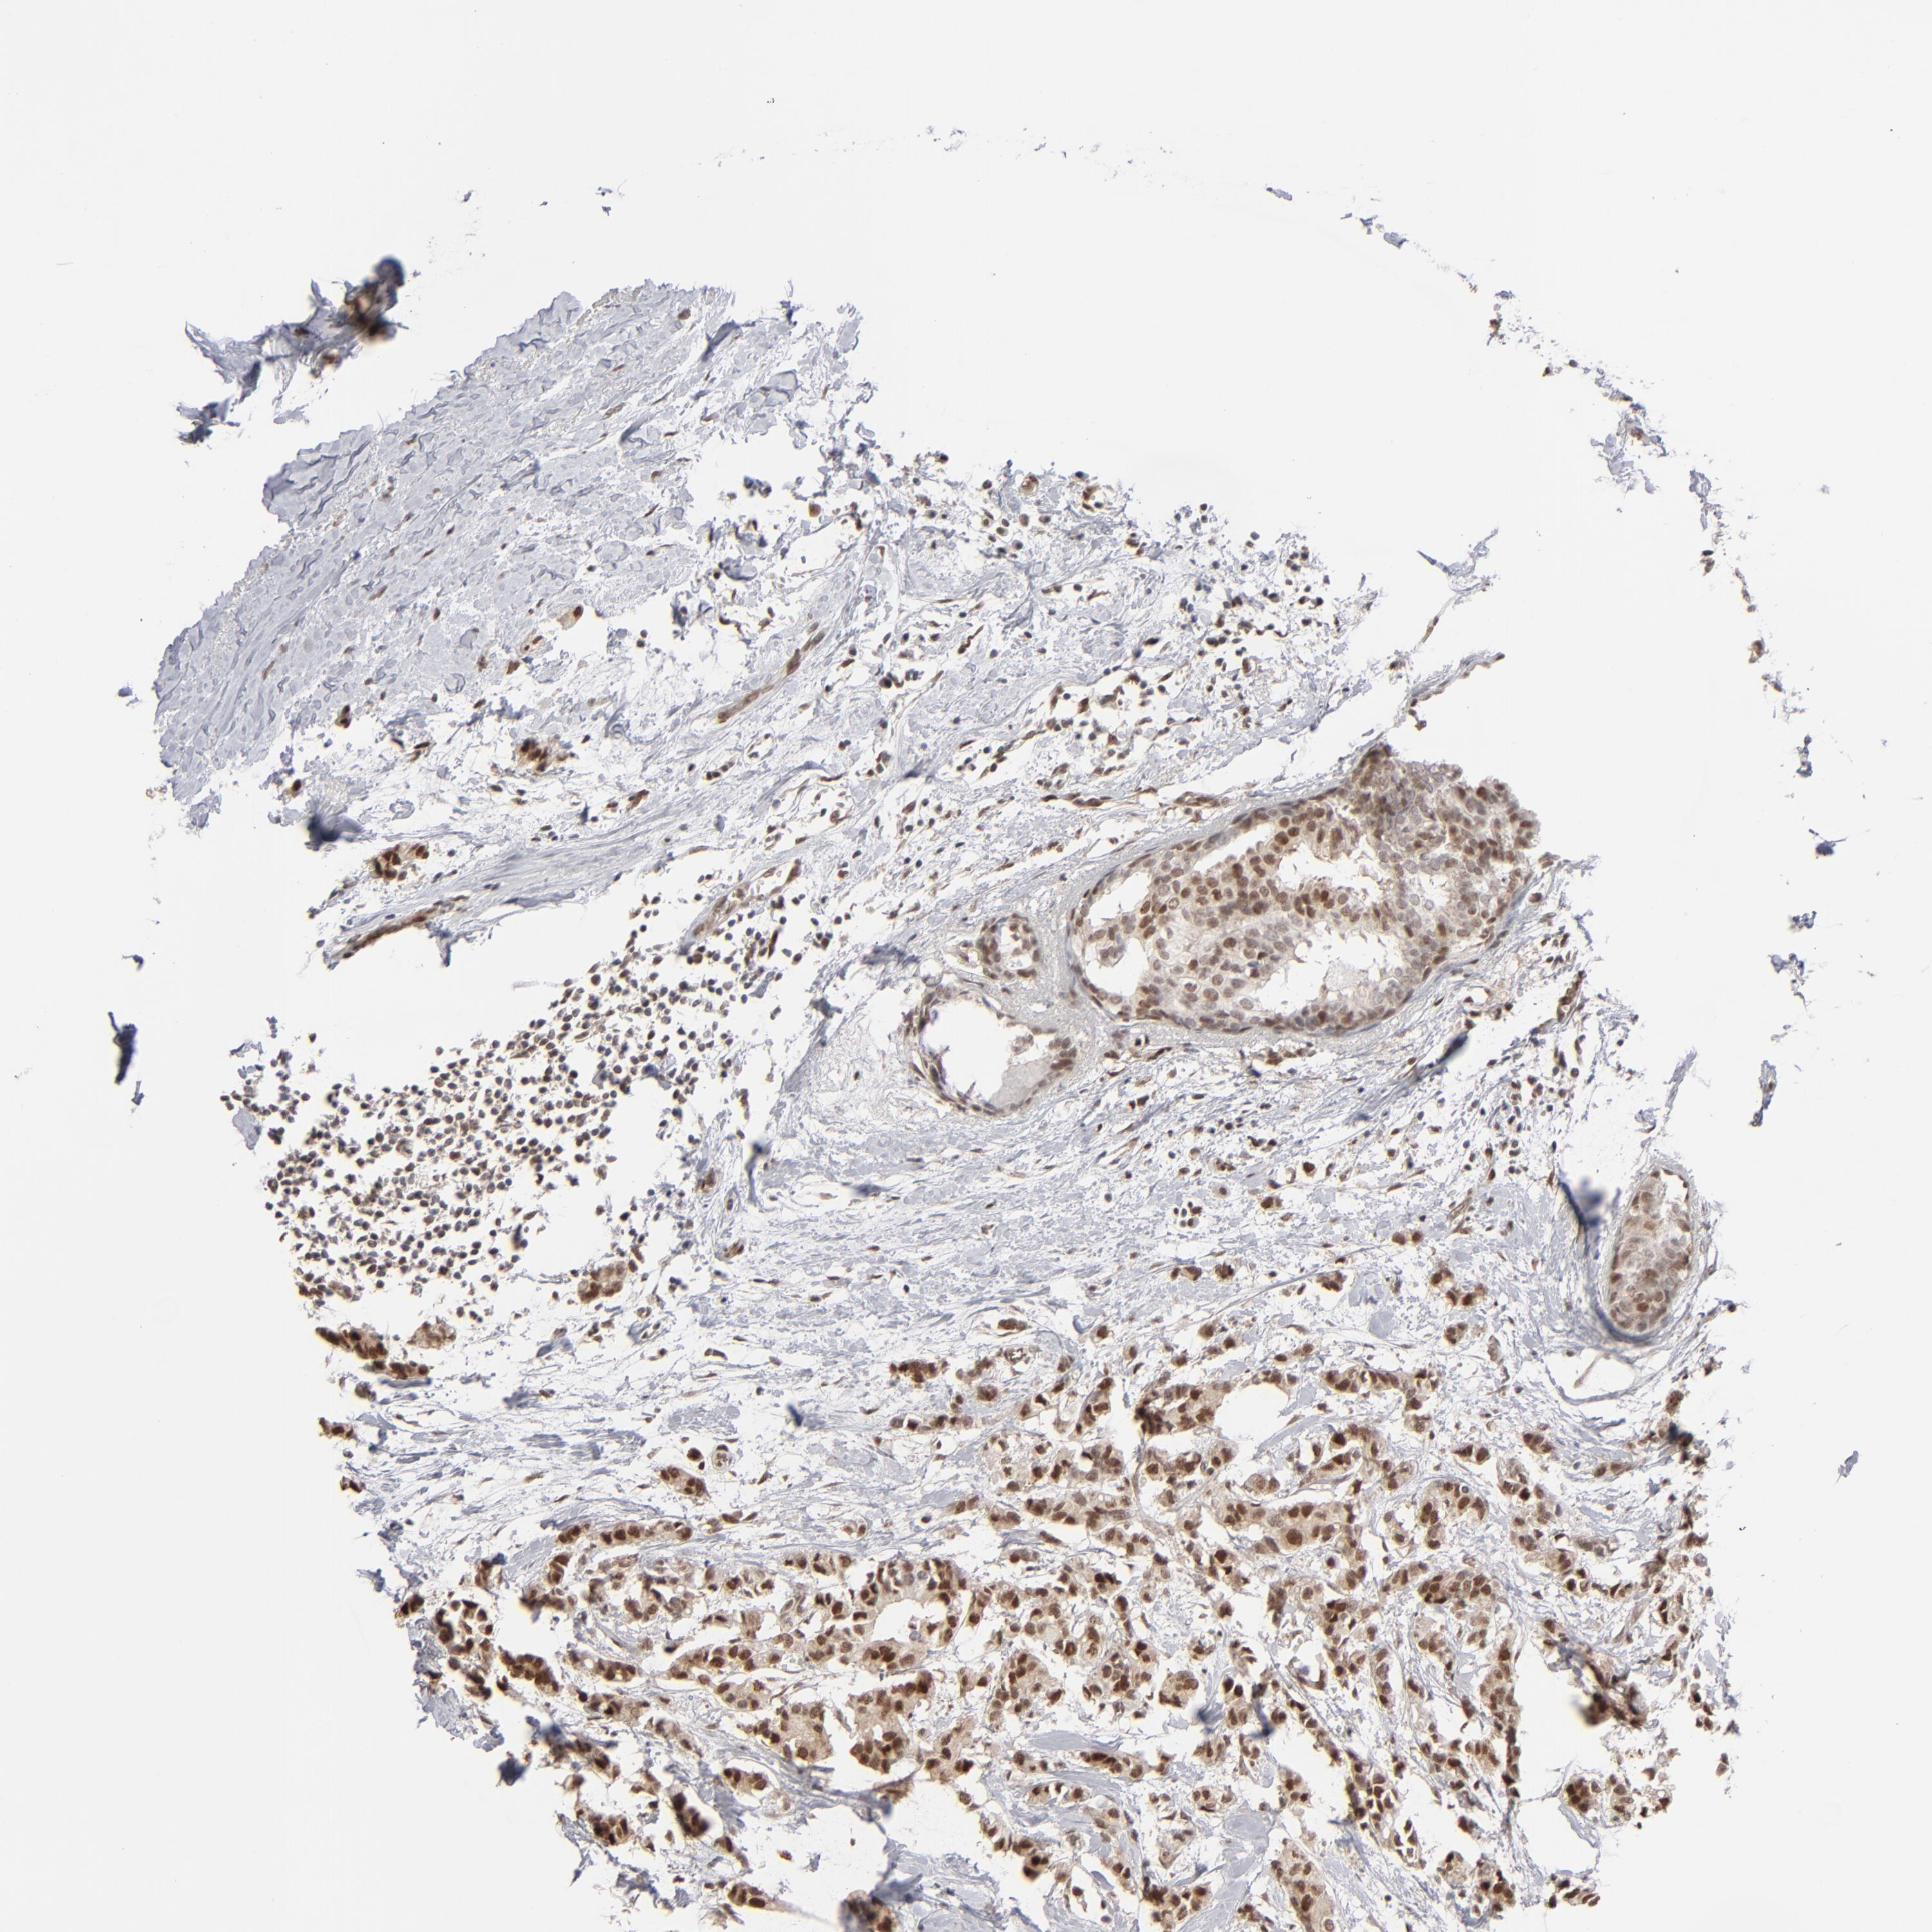

CANCER BREAST CANCER Show tissue menu

BRCA TCGA BRCA VALIDATION PROTEIN EXPRESSION